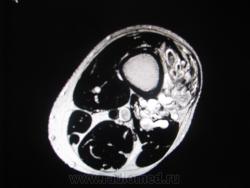

МРТ мягких тканей нижней трети левого бедра мужчна 46 лет.

Много лет беспокоит припухлость в задне-наружных отделах нижней трети левого бера, в последннее время выраженный болевой с-м, с диагнозом хронический гематогенный остеомиелит направлен на МРТ.При осмотре пальпируется образование вышеуказанных отделов, кожные покровы интактны.

Я бы заподозрил гемангиому с необходимостью дифференциальной диагностики с гемангиоперицитомой.

Остеомиелит - почему?? Кость, насколько можно судить по представленным изображениям, вообще интактна. Мы видим в мягких тканях образование "петлистой" структуры, скаладывается впечатление, что имеется его связь с сосудами. Смахивает на гемангиому. Исследование с контрастным усилением не делали?

Совершенного верно , это гемангиома. А почему остеомиелит,  для меня тоже загадка. Пациент что-то толковал насчет неровгогго контура кости на ренгене ( с собой не принес), может, на фоне этой штуки действительно неотчетливо визуализировалась кость? Хотя кроме лучевой картины для остемиелита есть масса других с-мов! Контрастировали, представлен один постконтрастный корональный  скан( последний  кадр) .Я думаю, здесь нужна селективная ангиография, для детального выявления питающего и дренирующего сосуда и работа ангиохирургов.